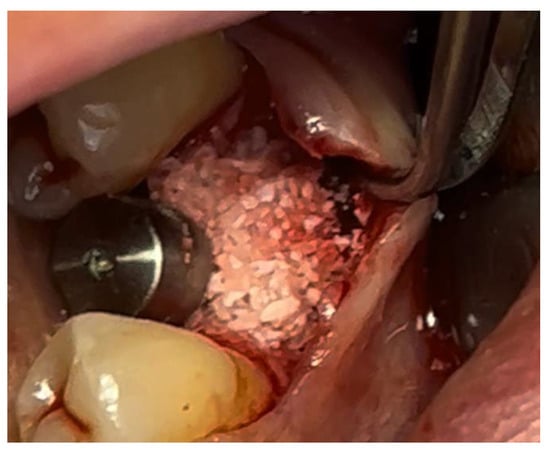

In a 49-year-old patient with ischemic heart disease, Glubran II was used as a stabilizing material for natural bone graft granules at a site rehabilitated with implant-prosthetic treatment, with the aim of achieving volumetric enhancement of the buccal bone. Following specific guidelines for surgical treatment of ischemic heart disease (4), implant therapy was carried out (Figure 8). Natural bone graft material (Bio-Oss®—Geistlich, Baden-Baden, Germany) was applied and stabilized with Glubran II. The application was made using an endodontic needle, depositing single droplets of the glue to cover the entire graft material before placing the prepared flap on top (Figure 9). This technique achieved stable graft fixation at the recipient site, demonstrating the efficacy of Glubran II for internal use (Figure 10).

Figure 9. Stabilization of bone regeneration material with Glubran II.